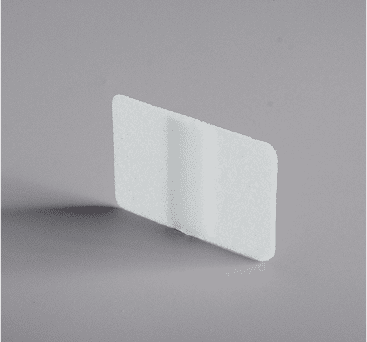

Membrane Sheet

Orbital Floor Plate

Lower Eyelid Implant